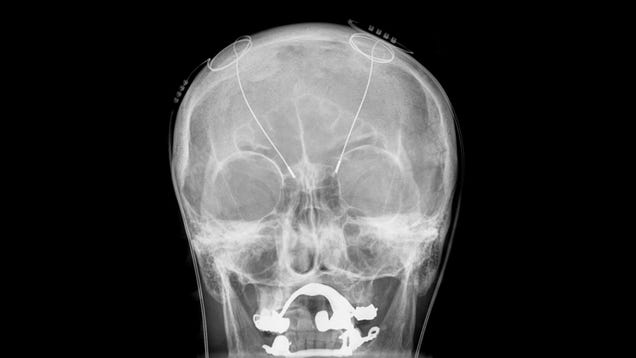

For some people with difficult-to-treat depression, a personalized, implanted device for the brain might provide relief when nothing else can, a new case study published Monday suggests. Researchers claim, for the first time, to have used custom-fitted deep brain stimulation to substantially alleviate a patient’s…